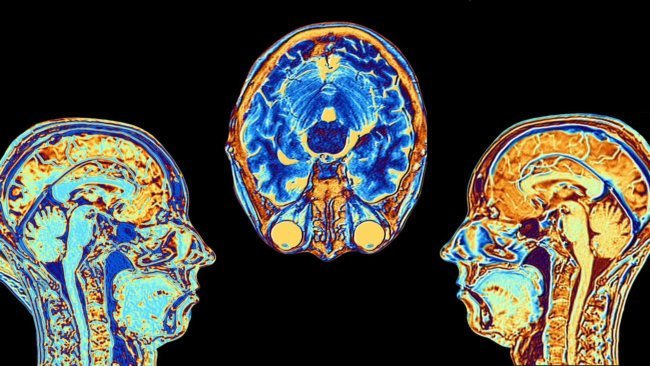

Ученые создали искусственный мозг с шизофрениейУченые создали подобие мозга с признаками шизофрении Детально изучать процессы, которые происходят в тех или иных органах, можно только на...

Откуда берется мораль и что на нее влияет?Повреждение определенной области мозга влияет на наши моральные суждения То, что общество считает «приемлемым» и...